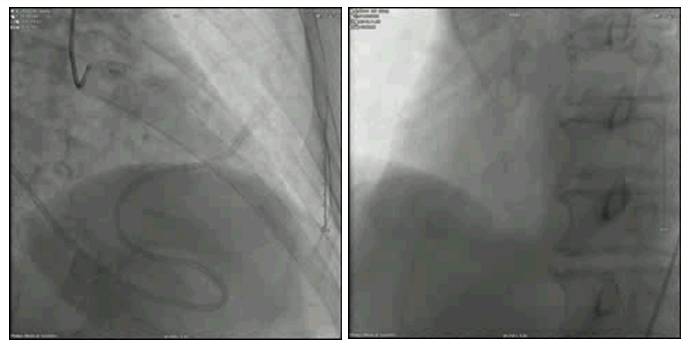

冠脉造影

2015.11.03 冠脉造影

治疗经过——顽固性心衰治疗历程

血运重建——

冠脉搭桥?

应用药物球囊?